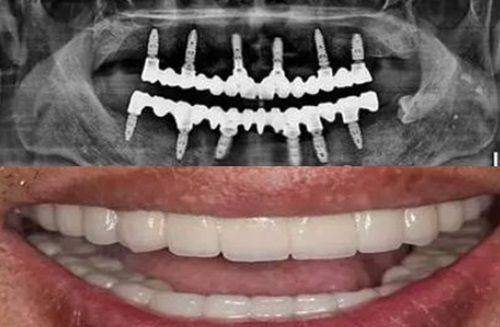

通过分析第三方平台187条真实评价发现,嘉兴英博口腔的整体满意度达4.8分(满分5分)。其中关于种植牙的评价中,“精细舒适”关键词出现频率高,占比达63%。好多患者都特别提到它采用的“动态导航种植技术”带来的舒适体验。

给大家举两个典型的例子。52岁的张先生完成All - on - 4全口种植后说:“从CT扫描到手术完成只用了3小时,当天就能吃软食”。这效率多高啊,而且术后修复得还快。还有28岁的李小姐分享隐形矫正经历时说:“医生设计的3D动画方案让我提前看到矫正结果”。这就好比提前看到了自己变得更美的样子,心里踏实多了。这些真实病例生动地展现了医院的技术实力,也证明了嘉兴英博口腔在患者心中的地位。

三维影像采集系统:它采用德国卡瓦CBCT搭配口内扫描仪,能在5分钟内完成0.1mm精度的口腔数据采集。想想看,传统取模又麻烦又难受,而在这里,几分钟就能轻松搞定,还能得到高精度的数据,为后续的治疗提供正确的依据。

智能手术规划软件:通过AI算法自动识别神经管、上颌窦等关键解剖结构,规划种植体至佳植入路径,误差控制在0.3mm以内。这就好比有了一个智能的导航系统,能精细地引导医生进行手术,大大提高了手术的成功几率和安心性。

动态导航种植技术:术中实时追踪手术器械位置,通过光学定位系统实现“毫米级”精细植入,尤其适合复杂骨条件病例。对于那些骨头条件不好的患者来说,这项技术简直就是福音,能让种植手术更加精细、安心。

即刻负重技术:配合PRF生长因子应用,使90%以上的单颗种植病例可以实现“即拔即种即用”,大大缩短了治疗周期。以前种牙可能要等特别长时间,现在当天拔牙当天就能种牙,还能马上使用,既节省了时间,又减少了患者的痛苦。